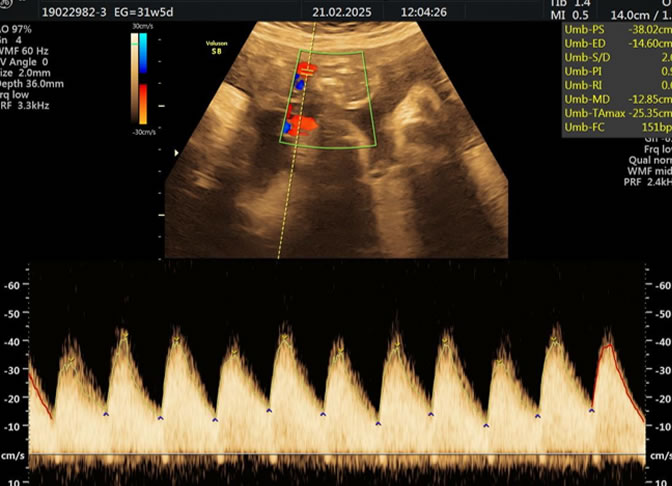

Es una técnica especializada de ultrasonido que utiliza el efecto Doppler para evaluar el flujo sanguíneo en el sistema circulatorio del feto y la madre durante el embarazo.

Se usa principalmente para evaluar el flujo sanguíneo en la placenta, el cordón umbilical y los vasos sanguíneos de la madre y el feto. Esto proporciona información valiosa sobre la salud del embarazo y la circulación fetal.

• Eco Doppler III Trimestre